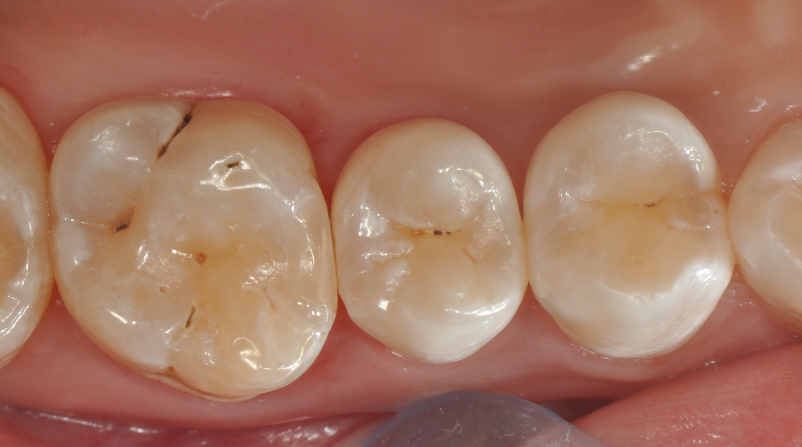

牙医-马小寒【实操病例】

右上6号牙位的近中,可见隐约龋坏

◆术后即刻照,如果邻面边缘出现悬突,可以使用12#手术刀去除,再配合抛光条抛光

◆术后撤离橡皮障后口内照片,术后1周复查,我们修正了边缘嵴的斜度及邻面轴线上的多余材料;复查是很重要的,能够发现第一次操作的时候遗留的不足,并且再次修正,保障了充填体的寿命。该案例也得益于改善了的成形片,修正了以往的成形片邻面龈缘区域材料残留形成过多的悬突材料,避免了术后龈乳头炎的发生!